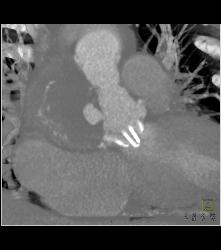

Dilated RCA After Reimplantation S/p Root Repair